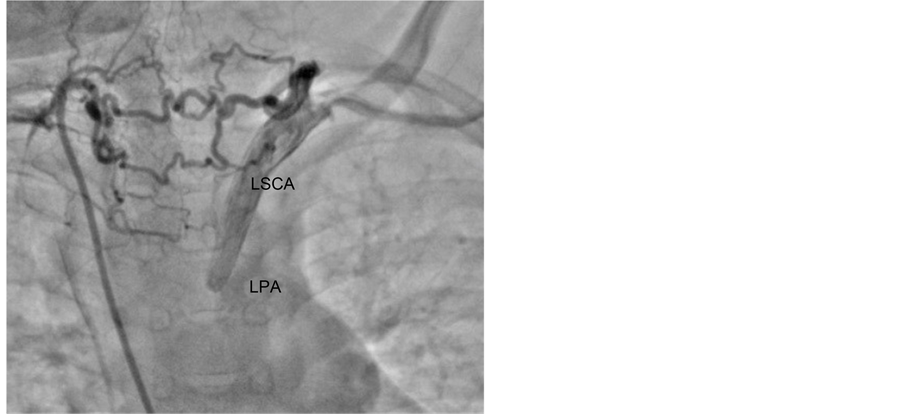

An 8-year-old child presented with bluish discolouration of lips and fingers since 3 - 4 months of his birth along with features of recurrent Lower Respiratory Tract Infection (LRTI). There was no history of cyanotic spells, weakness of any limbs, pain or numbness. There was no history suggestive of cerebral, vertebral or basilar insufficiency. On examination, patient had mild cyanosis and clubbing of fingers. Pulses in the left upper limb were weaker as compared to that in the right upper limb; however there was no significant blood pressure difference (Right (Rt) = 90/52 mm Hg, Left (Lt) = 87/50 mm Hg). Saturation of oxygen (Spo2) in Rt upper limb was 87% and that in Lt upper limb was 84%. Lower limb pressures and O2 saturation were also comparable with no significant differences. Cardio-vascular System (CVS) examination revealed a pansystolic murmur at apex. Chest X-ray showed a RAA with boot-shaped heart. Echocardiographic study revealed a typical anatomy consistent with TOF. There was sub aortic VSD with right ventricular outflow tract obstruction (RVOT) and pulmonary stenosis. Cardiac catheterization confirmed TOF with confluent and adequate Pulmonary Artery’s (PA’s). Aortogram confirmed the RAA with normal Right innominate, Right common carotid artery (RCCA) and Left common carotid artery (LCCA) with non visualization of LSCA; suggestive of isolation of LSCA (Figure 1). CT angiography confirmed the origin of LSCA from LPA (Figure 2) through an atretic Patent Ductus Arteriosus (PDA) and the LSCA was filling via a collateral artery originating from the descending aorta.

Figure 2. CT angiography 3D reconstruction showing Rt Innominate artery, RCCA and LCCA originating from RAA (a) and LSCA originating from LPA (b).

was no role of embolization as there was no pulmonary artery steal. It was supplied by collaterals from Descending Thoracic Aorta with no connection from the vertebral artery. So the patient did not have any vertebro-basilar insufficiency. In view of a weak pulse volume in left upper limb and anticipating symptoms in the limb as the child grows, we re-implanted the LSCA to LCCA. It was indicated by a better blood pressure and bounding pulses in the left arm in the follow up. Further study is needed to be conducted in similar cases and review should be done in order to accept re-implantation of LSCA as the line of management in such cases.